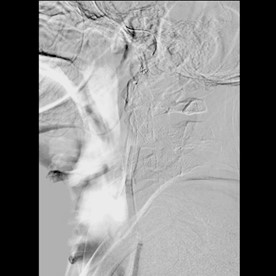

El paciente fue llevado a procedimiento endovascular con colocación de stent carotídeo izquierdo presentando recanalización de flujo en porcion obstruida arteria carótida interna izuiqerda (figura 2) y continuando terapia farmacológica con aspirina, clopidogrel y estatina. Presentó recuperación completa de los síntomas verificado en el último control a los 2 meses del episodio.

Figura 2A . Angiografía Cerebral: Stent a nivel de porción obstruida de carótida interna izquierda. B. Angiografía Cerebral: Recanalización de flujo posteior a Stent en carótida interna iziquerda.